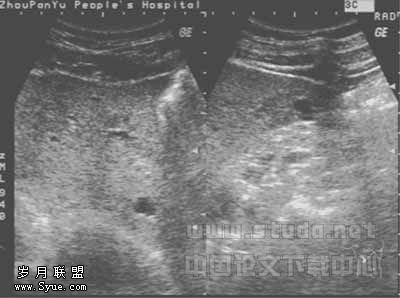

271例Ⅱ、Ⅲ级肝内胆管较均匀或节段性扩张,内径一般<3mm;Ⅱ、Ⅲ级及部分Ⅰ级胆管壁呈节段或弥漫不均匀增强、增厚,见图1,部分管壁出现不规则钙化斑,可伴有声影,胆管壁与门静脉分界不清,周围肝组织回声增强、增粗。其中4例合并被膜下小胆管囊状扩张,均<2cm,见图2。华支睾吸虫病在肝内的分布无明显特异性,但随着年龄的增长,其超声表现有由肝内胆管的扩张到胆管壁增厚、钙化、回声增强,周围肝实质回声增强、增粗这样一个趋势。

图2 华支睾吸虫病,被膜下小胆管囊状扩张